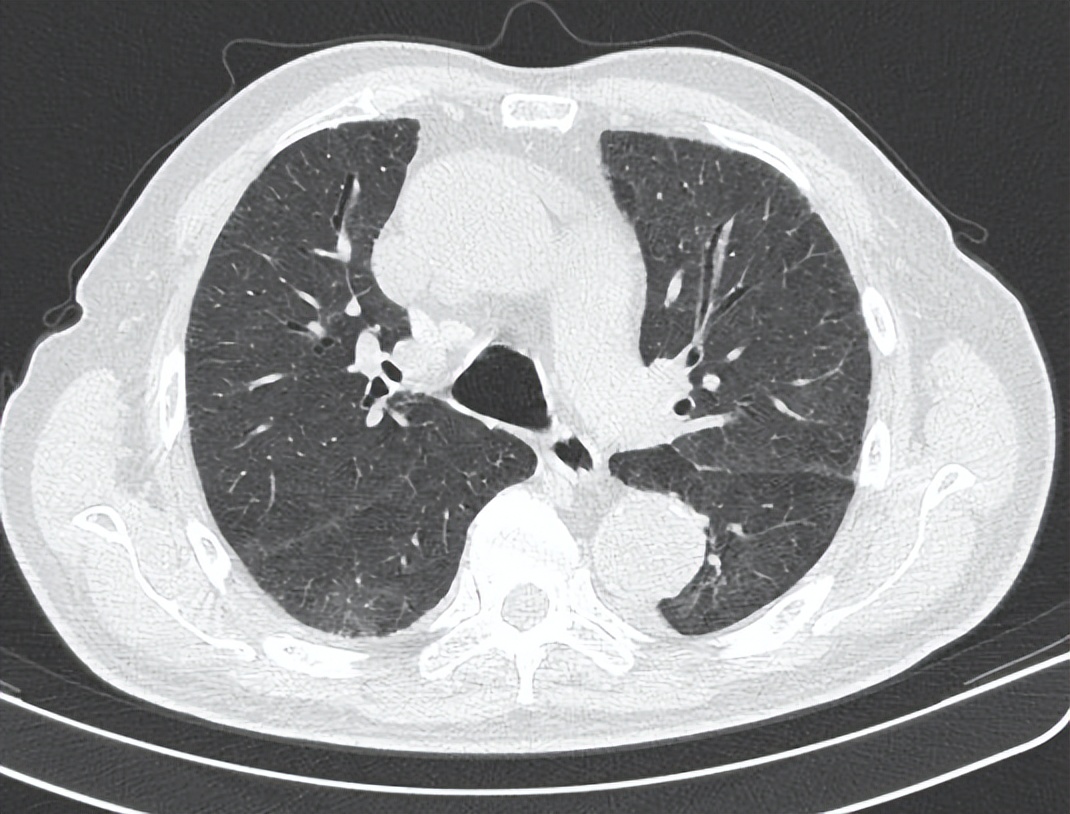

病程进展,症状加重……行气管插管机械通气,继续行抗感染治疗

治疗期间患者疾病进展,低氧血症及呼吸窘迫症状逐渐加重,氧合指数进行性下降,肺部病灶短期进展(图3)。因氧合无法维持,患者精神状态转差,于2023年1月31日胸片检查后行气管插管机械通气(图4),继续给予特治星(哌拉西林他唑巴坦)抗感染,辅以化痰、抗心衰、保肝等治疗。

图3